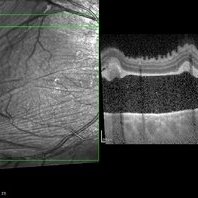

Multifocal Exudative Detachments Due to VKH

May 14 2014 by Avris Romario Diparaja Siahaan

OCT a 38-year-old man with multifocal CSR and inferior exudative retinal detachment on both eyes (Harada Syndrome).

Photographer: Avris Romario Diparaja Siahaan, Klinik Mata Nusantara

Imaging device: Heidelberg HRA + OCT Spectralis

Condition/keywords: multifocal central serous chorioretinopathy (CSCR), optical coherence tomography (OCT)